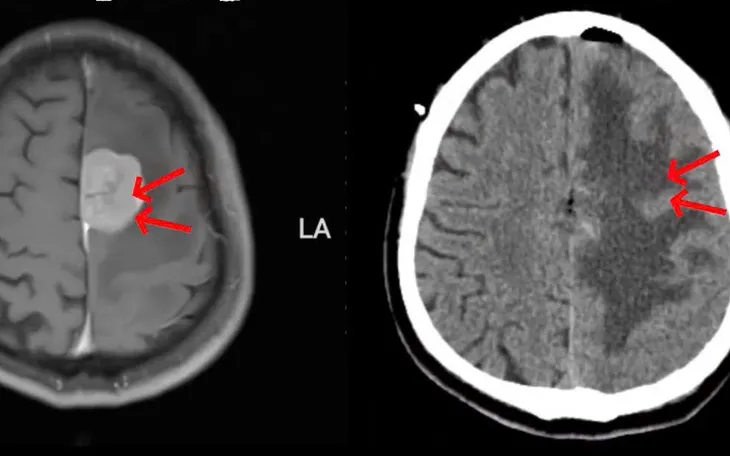

VTV.vn - Bệnh viện Trung ương Thái Nguyên vừa phẫu thuật u màng não liềm não ở người bệnh nam 43 tuổi bằng kỹ thuật vi phẫu, giúp cải thiện rõ rệt chức năng vận động.

Qua thăm khám lâm sàng và các phương tiện chẩn đoán hình ảnh, các bác sĩ xác định người bệnh mắc u màng não liềm não. Đây là khối u phát triển từ màng não, nằm ở vị trí sâu, sát các mạch máu lớn và vùng chức năng vận động quan trọng, tiềm ẩn nguy cơ cao trong quá trình phẫu thuật.